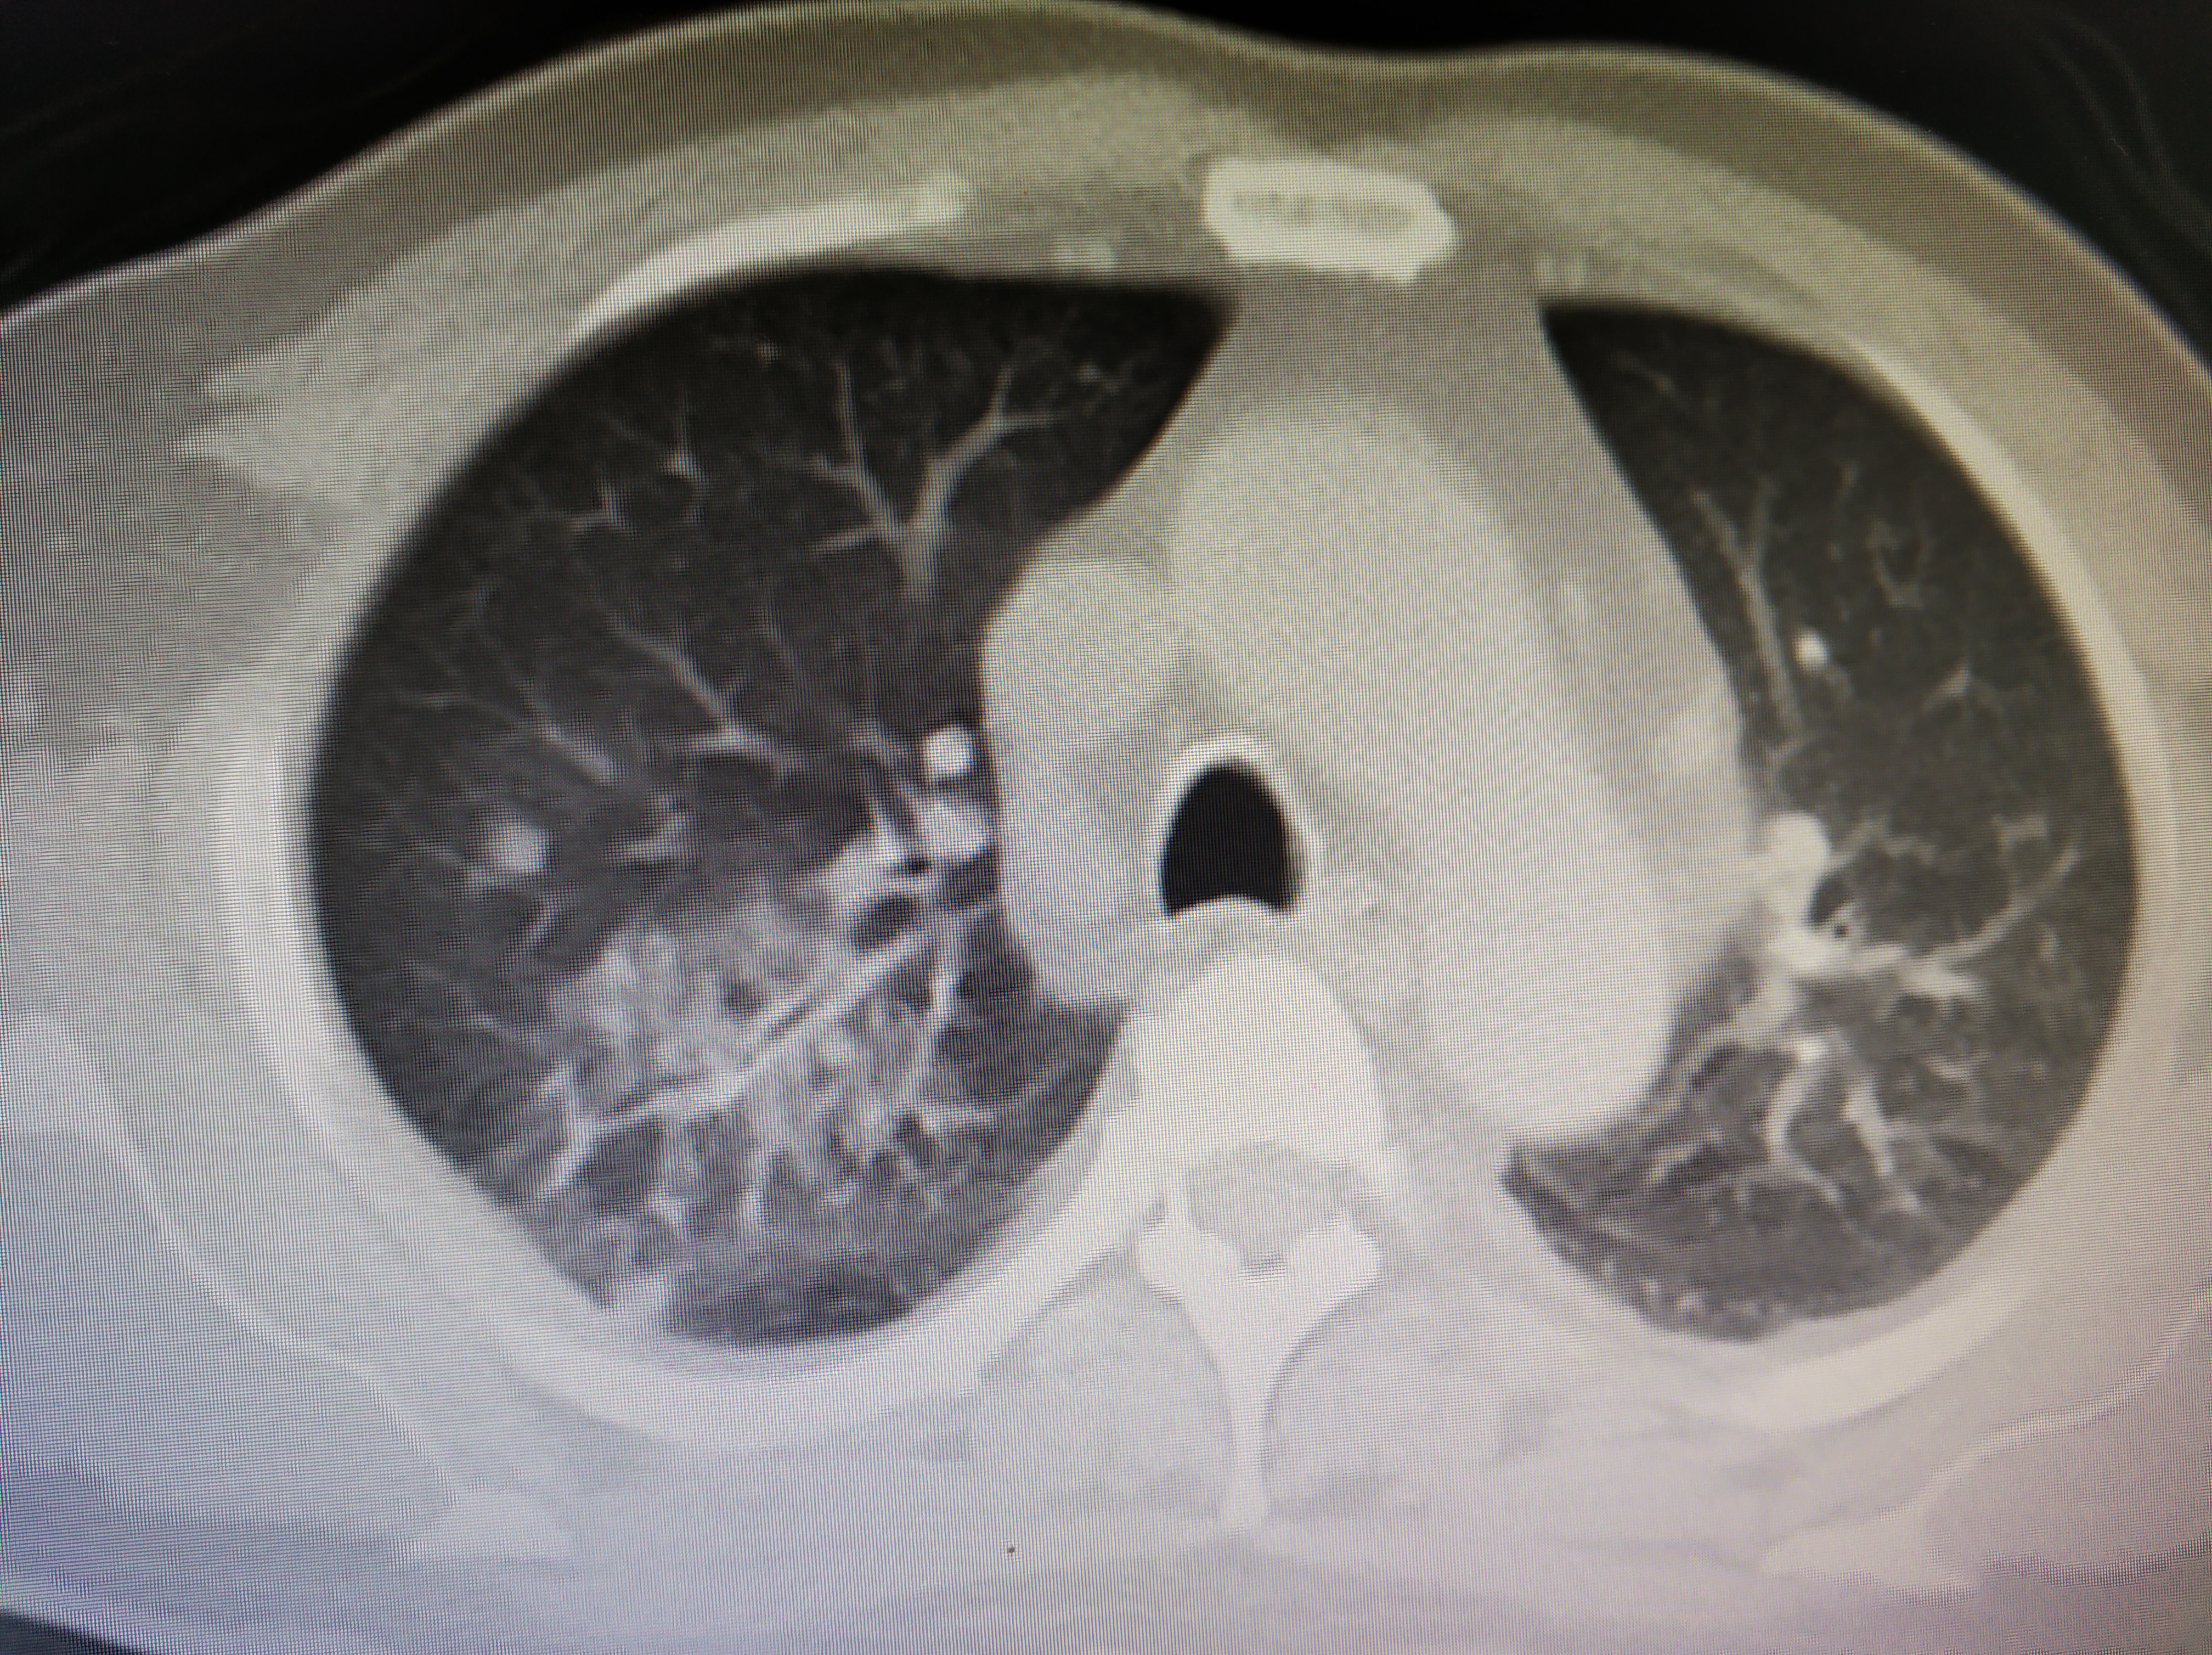

空洞型肺结核ct图

图片尺寸750x500